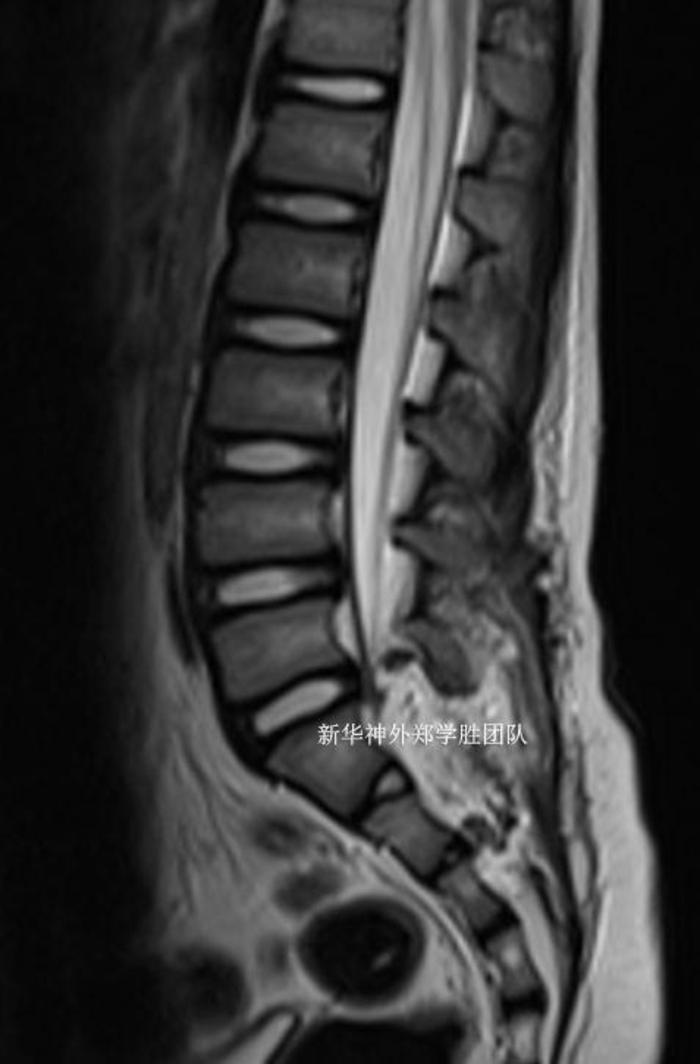

十岁儿童,因为经常腰痛、有时大便困难,检查磁共振发现巨大骶管囊肿,从腰5下缘延伸到骶4上缘。

CT检查还发现严重的脊柱裂,整个骶管全部裂开。

术后复查磁共振,骶管囊肿完全封堵。手术切口仅4厘米,患儿术后几乎没有什么疼痛,两周下床活动自如,治愈出院。没有任何神经功能障碍。